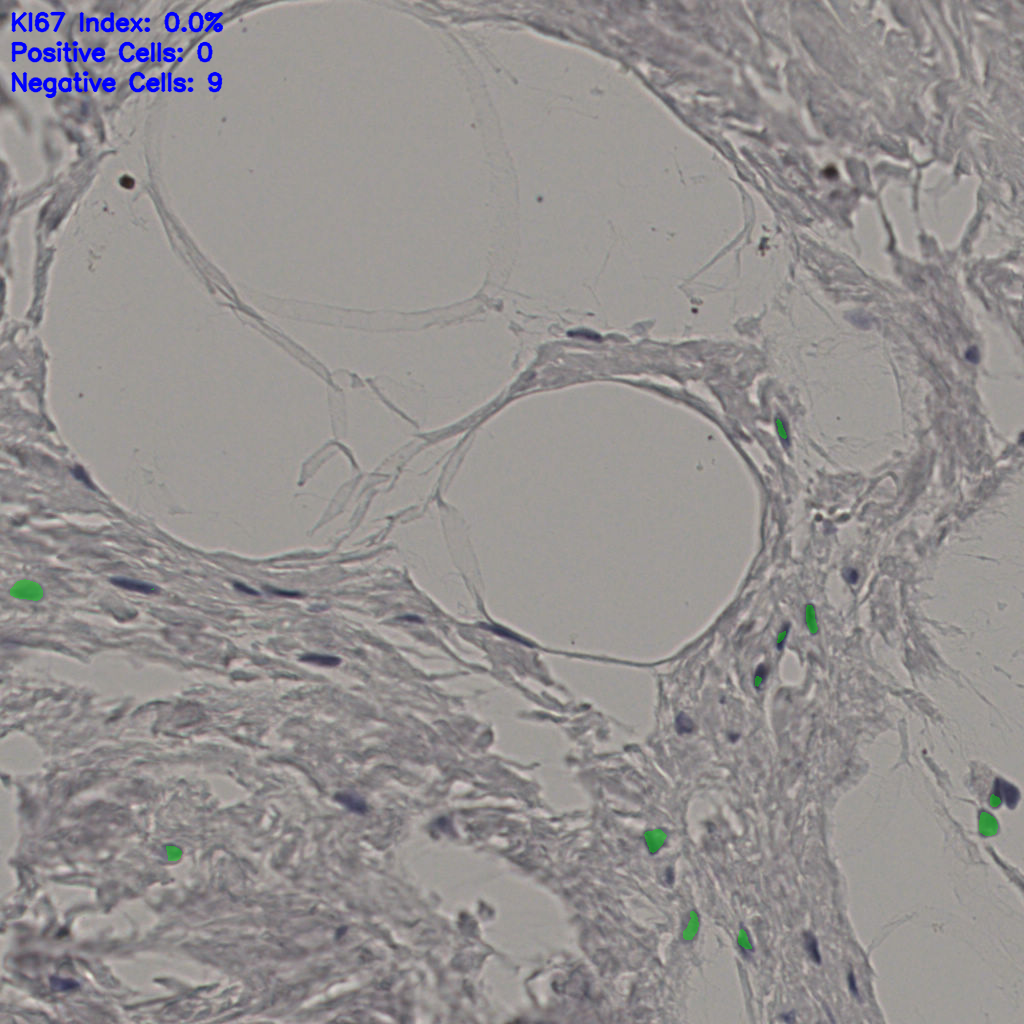

Ki67 指数

阴 19502

阳 1093